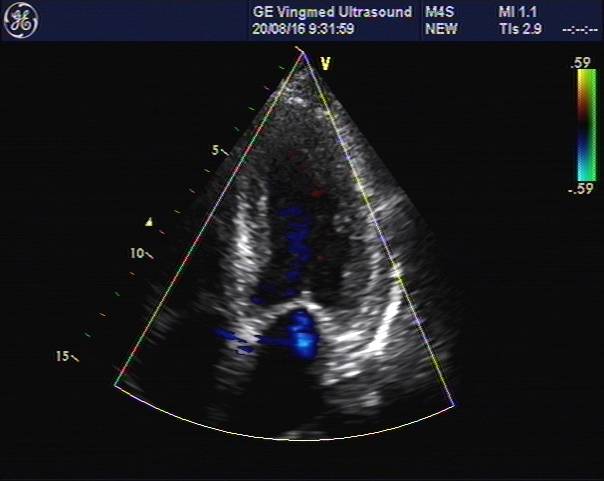

心脏彩超

主动脉根部:30

左室舒张末:40

左室收缩末:26

左房: 34

室间隔: 17

左室后壁: 16

E:79,A:109

EF:64%

E/E’:26